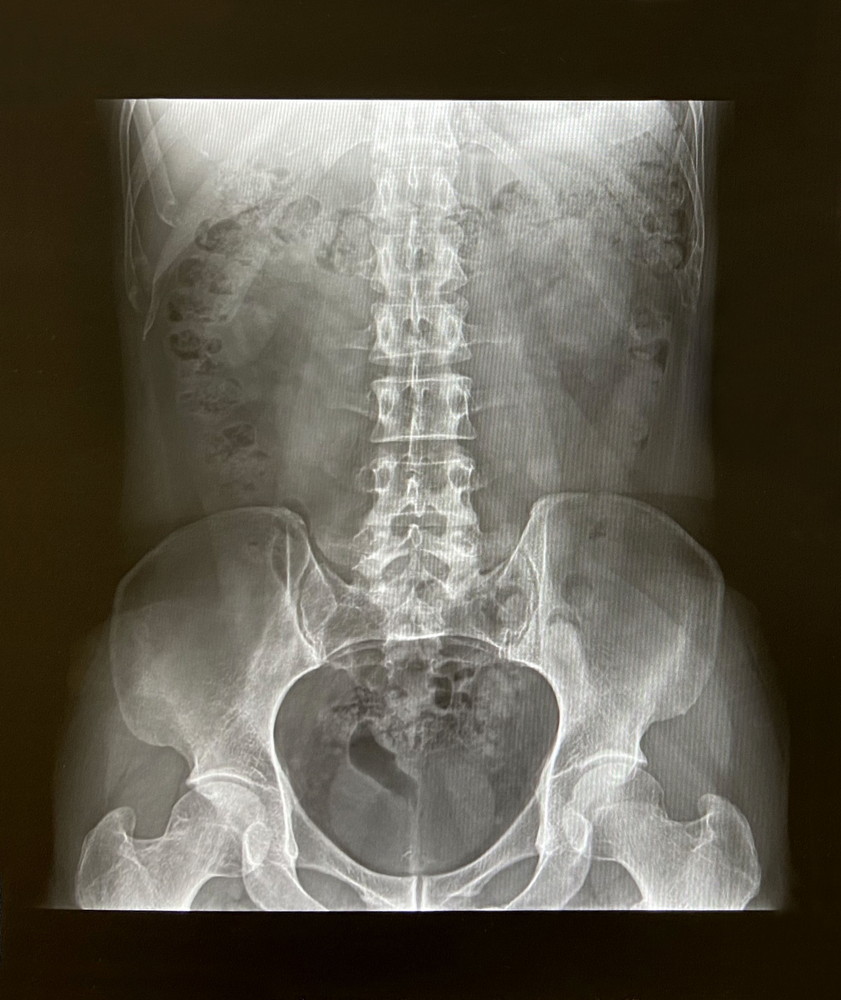

骨のズレってなに!?

さて、本題に入りますが、カイロプラクティックや整体院などで骨がズレてますね、歪んでますねと言われることはままあるかと思います。

ここで、施術者側と患者さん側でズレやゆがみに対するイメージに差があることが多いです。

患者さん側はズレているというと、静止画像(レントゲン)などで数cm単位で位置的な変位があると捉えがちですが、数cmレベルの変位となると亜脱臼や脱臼といった類になってしまい、あったとしたらそれは激痛を伴うはずです。

カイロプラクティックでは、骨の静止位置的な変位も考慮しますが、それよりも関節の動的平衡バランスをみています。

関節の動きの量と質を触知して判断しているので、カイロプラクティックでいうズレとはほんの数mm単位の位置的な変位と関節可動性の動的平衡バランス(質と量)の機能的な不調和をいいます。

静止画像によって変形や位置的な異常などの整形外科的な問題がないかの確認はもちろん大事ではありますが、カイロプラクティックでは動的すなわち機能的な異常を見つけ出し、それを調整して取り除いていくのが得意です。